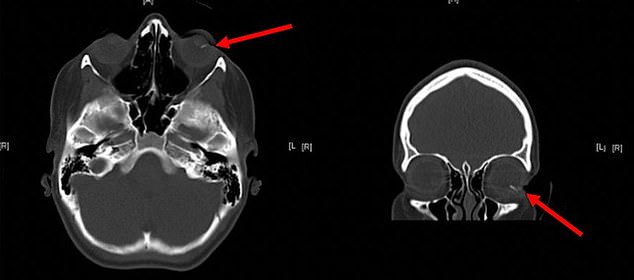

She was taken to the hospital immediately where she had emergency surgery to pluck two parts of the lead pencil from her right eye.

One part was just millimeters from her retina, it is a crucial piece of tissue at the back of the eye that converts light into imagery if the damage can make you blind.